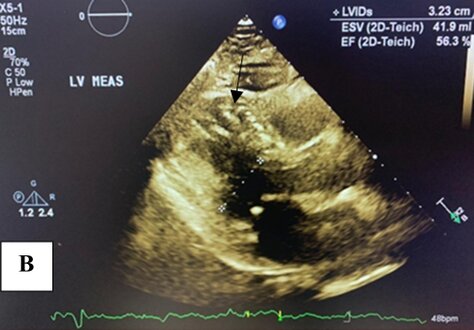

Left ventriculography demonstrated a normal-sized left ventricle with apical akinesis and basal hyperkinesis, resulting in the characteristic "apical ballooning" pattern seen in Takotsubo syndrome (TTS). An apical thrombus was also identified (Figure 4(a) and (b)).

Figure 4. Left ventriculography demonstrating apical akinesis and basal hyperkinesis, consistent with Takotsubo cardiomyopathy. An apical thrombus is clearly identified at the left ventricular apex (black arrow) in both diastole and systole views. (A) End-diastolic frame; (B) end-systolic frame.